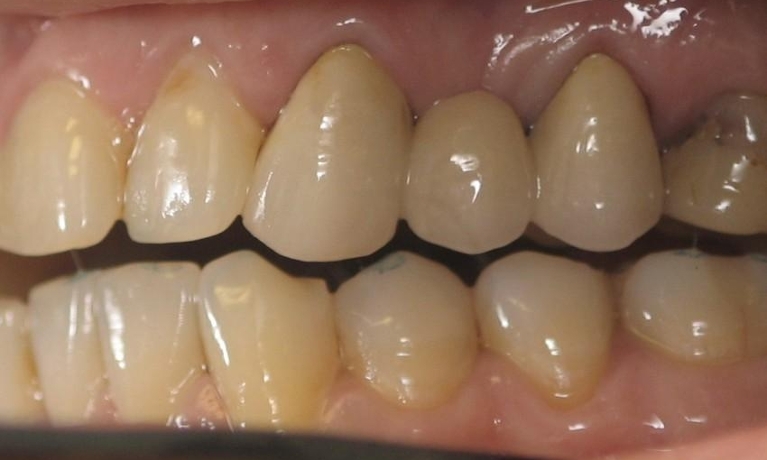

Smile Gallery

Are you considering dentistry at Michael J Nelson DDS? If so, we’d like to invite you to browse our Smile Gallery. Our dental team can improve your oral health and help you attain the attractive smile you’ve always wanted.